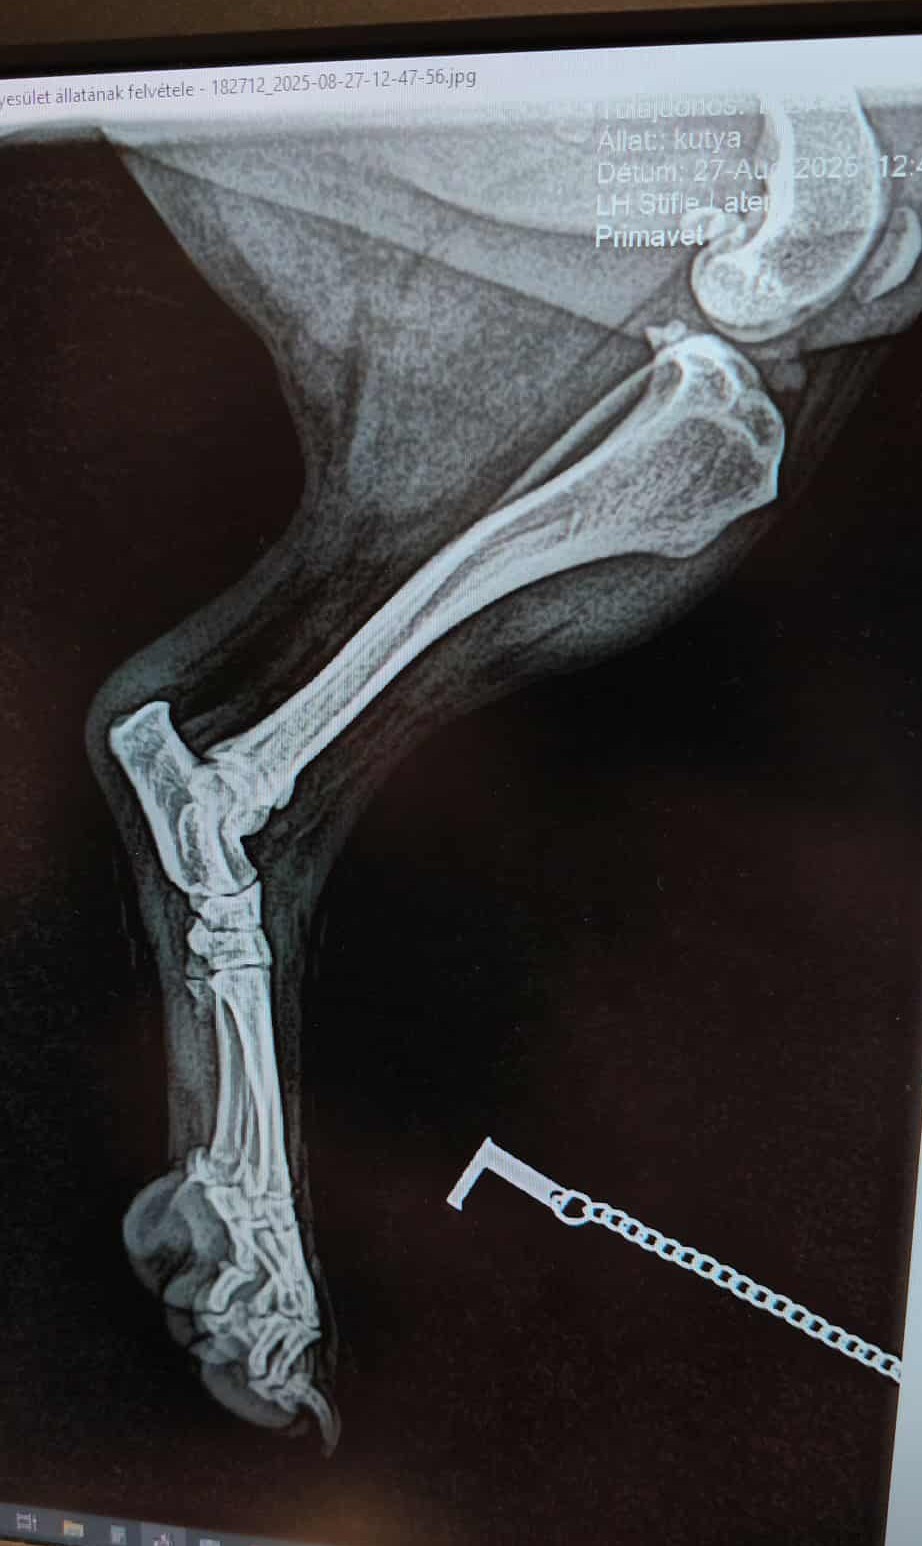

Heute Morgen (27.08.2025) erhielten wir einen Notruf für eine schwerverletzte kleine Hündin, die hier in Örkény überfahren wurde und einfach achtlos liegen gelassen wurde. Dank eines bediensteten der Stadtverwaltung, der uns bereits des öfteren über Notfälle informierte, konnten wir die kleine Hündin sichern und fuhren mit ihr umgehend in die Klinik. Sofort wurden die notwendigen Untersuchungen und Röntgenaufnahmen gemacht. Die kleine Hündin erlitt einen komplizierten 3-fachen Beckenbruch, der sofort operativ behandelt werden muss. Ersten Schätzungen der Klinik zu folge werden die Klinikkosten sich auf ca. 390.000,00 Forint ( ca. 990,00 Euro ) belaufen. Weil wir in der Klinik sofort einen Namen angeben müssen, haben wir sie ENYA getauft.